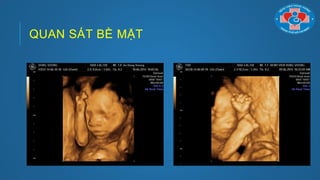

Quan sát bề mặt: (Sử dụng tốt nhất trên mặt, cột sống, tứ

chi)

QUAN SÁT BỀ MẶT